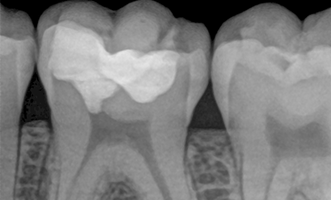

Initially, the patient was treated in a general dental practice where the doctors detected deep secondary caries closely located to the dental nerve of a bottom left molar. Since preserving the vitality of the tooth nerve was top priority, the patient was directly referred to Georg Benjamin’s specialized endodontic practice to undergo treatment.

Dr. Benjamin diagnosed a symptomatic reversible pulpitis and initially performed a cold test to determine whether the dental nerve was still fully vital. As the cold test turned out positive, Dr. Benjamin decided to perform a partial pulpotomy to remove the deep secondary caries and preserve the vitality of the tooth nerve.

Since the infected bottom left molar already contained a filling, Dr. Benjamin removed the old filling material with the help of a diamond bur. After this, he removed the secondary caries by using an EndoTracer, but then switched to a hand instrument to precisely clean the remaining tooth substance.